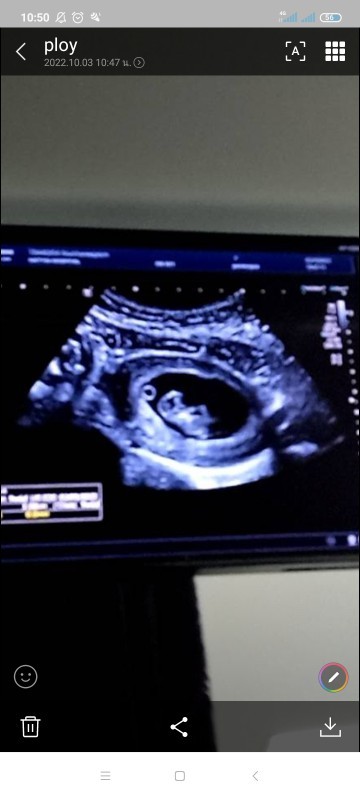

ของบ้านนี้ก็9w จ้าา เห็นครั้งเเรก ก็ตื่นเต้นเหมือนกัน

Post reply image